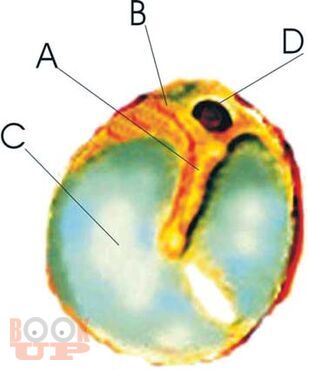

Хронический средний отит

Данное руководство по Хроническому среднему отиту выполнено на кафедре послевузовского обучения специалистов по болезням уха, горла, носа Московской медицинской академии им. И.М.Сеченова. В результате последовательного анализа особенностей патофизиологического развития хронического воспалительного процесса в среднем ухе были выявлены три основных разновидности «порочного круга» его развития, которые и оказались основой хронического течения воспалительного процесса. Это позволило выявить патогенетические закономерности развития хронического среднего отита, разработать современные патогенетически обоснованные методы лечения для разных его форм и стадий. В результате, была составлена патофизиологически обоснованная классификация хронического среднего отита, которая значительно облегчает и ускоряет диагностику, помогает подбору наиболее результативного лечения и способствует выработке эффективных мер профилактики, как в условиях клиники, так и в поликлинических условиях. Новые методики защищены Российскими патентами. Данное руководство по Хроническому среднему отиту рекомендовано Учебно-методическим объединением по медицинскому и фармацевтическому образованию вузов России в качестве учебного пособия для практикующих врачей – специалистов по болезням уха, горла, носа.